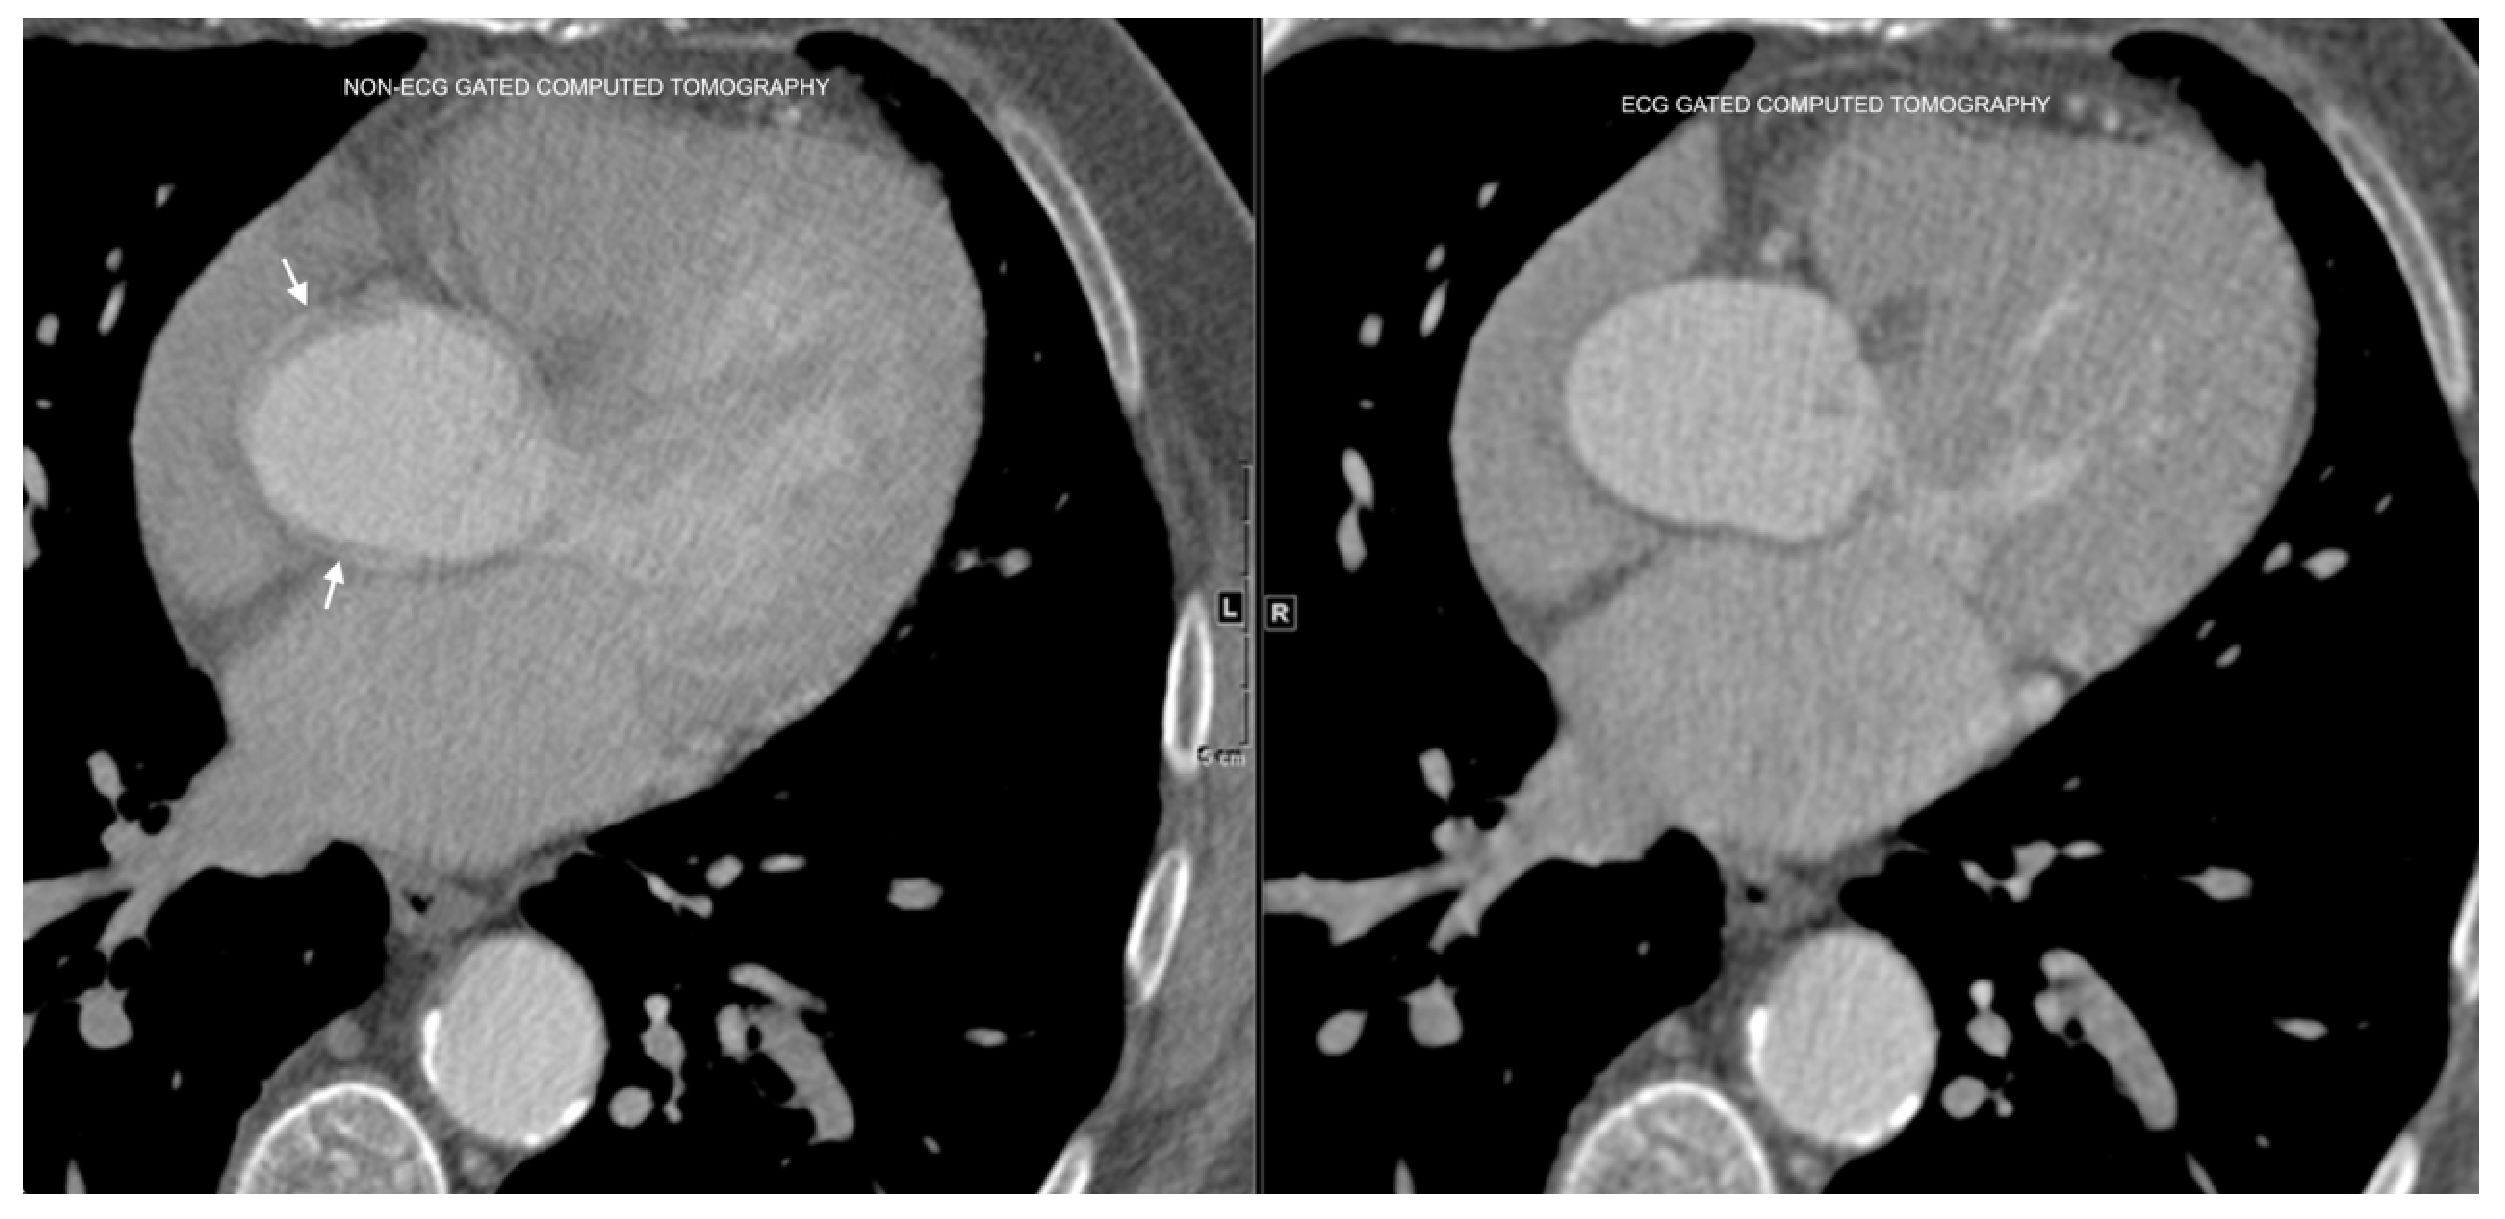

The differences between ECG-gated and non-ECG-gated chest CT scans, and the associated motion artifacts, are illustrated in Figure 3.

Figure 3. Comparison of ECG-gated and non-ECG-gated chest CT scans of the aorta. Arrows denote the blurry borders of the ascending aorta in non-ECG-gated images, which appear sharper in ECG-gated images. Motion artifacts in non-ECG-gated scans pose significant challenges in segmentation tasks.